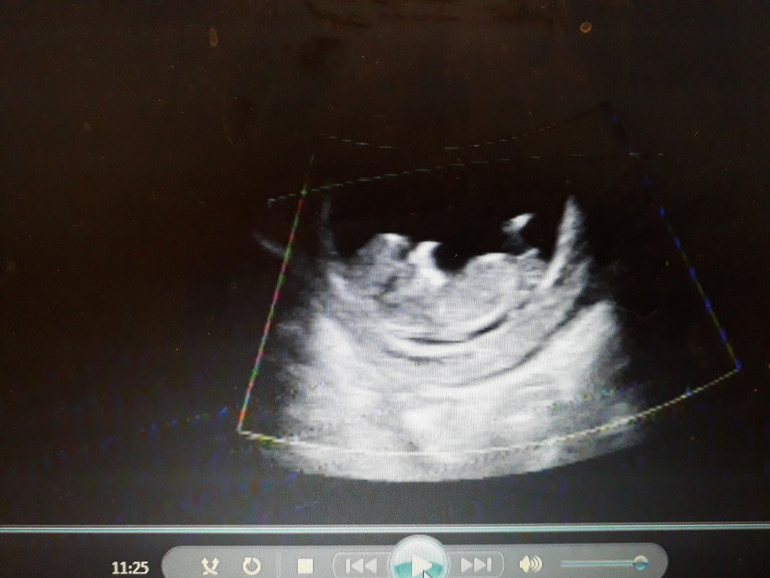

У нас вот такая же проблема...на двух УЗИ была, на первом девочку пообещали...а на втором в 13 недель врач сказал мальчик. А мне так доченьку хочется ( уже 2 сына) вот наше фото с первого скрининга